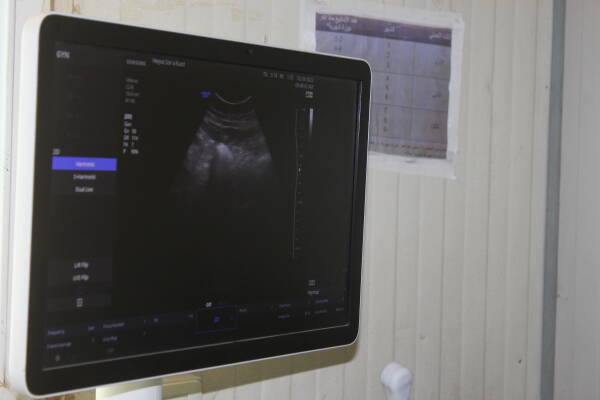

نوال الشرابی درباره‌ی خدماتی که ارائه می‌دهند گفت: «کار ما متوقف نشده و خدماتی که ارائه می‌دهیم تغییری نکرده است. ما به زنان باردار و مریض کمک کردە و به آنها خدمات درمانی و کمک‌های اولیه ارائه می‌دهیم و در کمپ تجهیزات پزشکی برای مراقبت از زنان و کودکان داریم و داروهای لازم نیز موجود است. هر چند ما با خطر مواجە هستیم، اما این وظیفه‌ی ماست و هرگز عقب نخواهیم نشست، چه جنایتی مرتکب شده باشند و چه نشدە باشند، به آنها کمک و خدمات بهداشتی ارائە دادە و به وظیفه‌ی انسانی خود عمل می‌کنیم.»